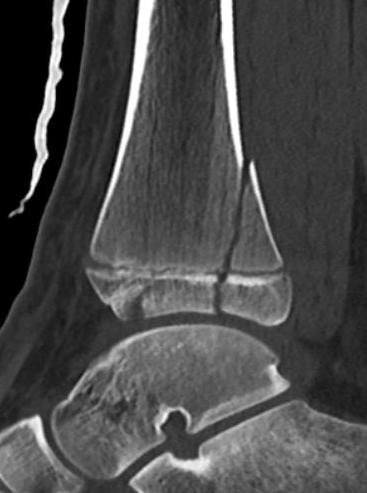

Triplanar Fracture

Definition

Fracture in coronal, sagittal and transverse planes

- crosses epiphysis

- passes through growth plate

- extends into metaphysis

Xray

AP xray: Salter-Harris type III / Tillaux

Lateral xray: Salter-Harris Type II

CT

Coronal images: Salter-Harris type III

Sagittal images: Salter-Harris type II

Axial images: 3 point star